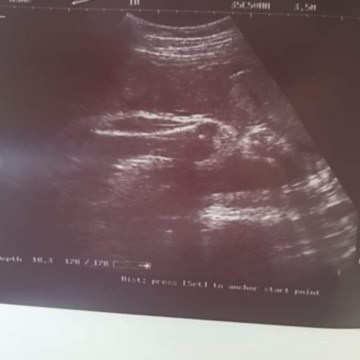

แม่บ้าน นี้35+1แร้วค้ะน้ำหนักลูกในท้องพึ้งใด้1570กรัมยุเลยแม่ๆคนใหนมีวิธีเพิ้มน้ำหนักลูกในท้องแนะนำหน่อยค้ะกัวลูกออกมาน้ำหนักไม่ถึงเกน

แอลตร้าซาวด์ไม่แน่นอนคะ คุณหมอซาวด์ให้กล่อนคลอด 2600 น้องออกมา 3500แนะ กินกล้วย นม ไข่แดง เพิ่ม นน น้องคะ